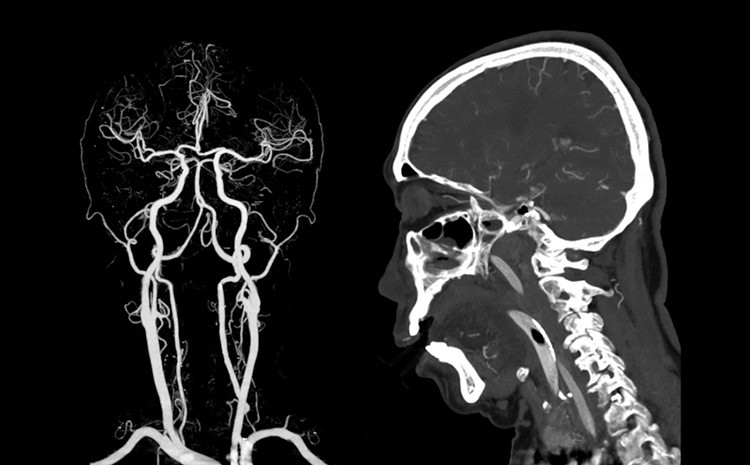

A angiografia cerebral é uma das ferramentas mais impressionantes da medicina moderna, principalmente por permitir algo que parece impossível: observar o sangue circulando dentro do cérebro em tempo real. É como colocar o órgão em “câmera lenta” e enxergar detalhes que, a olho nu, jamais seriam percebidos. Esse processo transforma informações invisíveis em imagens claras, revelando caminhos, desvios e pequenas irregularidades que podem alterar completamente um diagnóstico.

Muito além de uma simples imagem, a angiografia mostra movimento. Cada passo do contraste dentro dos vasos revela a coreografia natural da circulação cerebral. Essa sequência, quando analisada por especialistas, ajuda a entender como o sangue se comporta, onde encontra resistência e quais áreas mostram sinais de sofrimento. A técnica proporciona uma visão dinâmica, que muitas vezes define a estratégia de tratamento.

A maior beleza desse exame está justamente no detalhe. Minúsculos vasos, imperceptíveis em outros métodos, tornam-se protagonistas. Isso faz toda a diferença, porque muitas doenças graves começam nesses pequenos trajetos. A angiografia não apenas vê; ela interpreta.

Quando o contraste é injetado, a magia acontece. A partir daquele instante, os vasos cerebrais ganham destaque nas telas, e o sangue parece se mover em câmera lenta. Essa desaceleração visual é essencial porque permite observar o fluxo de forma segmentada, quase como se fosse um filme detalhado do sistema vascular. O contraste ilumina caminhos que antes estavam escondidos, revelando padrões que contam histórias sobre a saúde do cérebro.

A análise desse movimento é extremamente rica. O profissional identifica se o fluxo segue um caminho natural, se há pontos de estreitamento ou se o sangue encontra rotas alternativas. Cada detalhe importa. Um vaso que preenche mais devagar pode indicar uma alteração; um trajeto que não aparece pode sugerir um bloqueio. Nada passa despercebido.

O interessante é que, mesmo sendo um exame altamente tecnológico, a interpretação dessa “dança” exige experiência clínica. A imagem mostra, mas é o olhar treinado que entende. O contraste não apenas revela estruturas; ele traduz comportamentos, e isso torna a angiografia uma verdadeira arte dentro da medicina diagnóstica.

Com a circulação cerebral exposta em detalhes, a angiografia permite encontrar segredos que outros exames não mostram. Pequenas malformações, variações anatômicas, fragilidades de parede e irregularidades no fluxo tornam-se claramente visíveis. Essa precisão é fundamental para o planejamento de cirurgias, procedimentos minimamente invasivos e decisões clínicas urgentes.

Muitas vezes, o exame revela informações que mudam completamente a condução do caso. Um trajeto que parecia normal em outros métodos pode apresentar nuances importantes na angiografia. Essa capacidade de revelar o “não dito” é o que torna a técnica tão especial. É um exame que vê mais longe, mais fundo e mais rápido.

Além disso, a angiografia oferece algo único: a possibilidade de comparação dinâmica. Os profissionais conseguem observar como o fluxo se comporta ao longo do tempo, identificando padrões que indicam adaptação ou sobrecarga vascular. Esses detalhes são peças-chave na compreensão de doenças complexas, auxiliando na escolha do melhor caminho terapêutico.